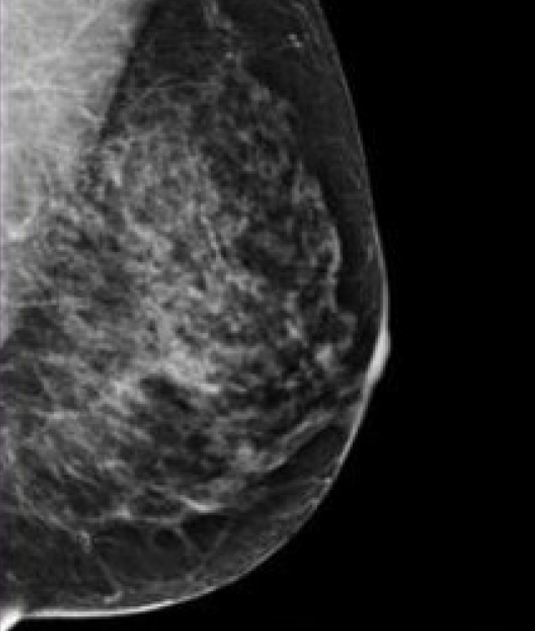

Previous Image Next Image Breast-Tissue-3 More glandular and fibrous tissue present. This can make it hard to see small masses.